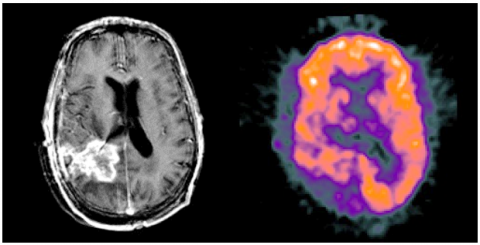

Today, medical imaging plays an essential role in clinical diagnosis and treatment. CT images, for example, are widely used in fractures because they can record bone condition. MRI scans can be used to diagnose brain diseases such as brain tumors and the like. CBF (Cerebral Blood Flow) images can objectively reflect changes in the tension and tension of cerebral arteries. SPECT images can measure the biological activity of cells and molecules. However, these images have limitations that may limit their use in real applications. Single-photon emission computed tomography (SPECT) images, for example, cannot be clear enough to absorb brain structures. Therefore, SPECT images are always used with computed tomography (CT) or MRI images for clinical diagnosis. Finally Medical images (http://www.med.harvard.edu/AANLIB/home.html) were captured by the SEWT method [13].

In Figure 2, examples of such images are shown as input images. There are four images in each row, with the first two images being the same as the input images and the second two images being noisy images with a standard deviation value of 10.

(a). Input images

(b). Noisy images with $\sigma=10$

(c). Input images

(d). Noisy images with $\sigma=10$

(e). Input images

(f). Noisy images with $\sigma=10$

Figure 2. Input images and noise images